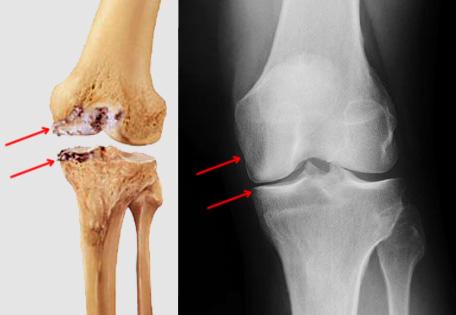

Indications for Total Knee Replacement -Severe os...

Total knee replacement (TKR) is considered necessa...